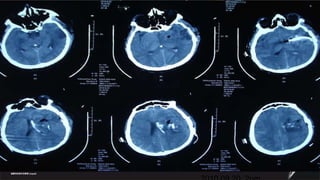

Case  Male ,47ys 2010.09.17  9:17PM Sudden onset of headache and hemiparalysis Muscle strength 0 degree, GCS11 .  BP180/120mmHg

2010.09.18  1:11:17PM

2010.09.18  6:07PM

2010.09.20  2pm

2010.09.25  9AM

2010.09.29  11AM

Case Male,47ys 2010.09.17 9:17PM Sudden onset of headache and hemiparalysis Muscle strength 0 degree, GCS11 . BP180/120mmHg